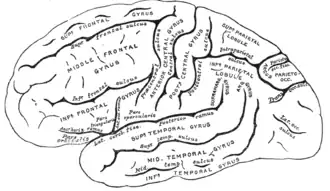

- Lateraal deel

Het laterale (aan de buitenkant gelegen) deel kan (wederom van boven naar onder, gerekend vanaf de fissura lateralis, de groeve van Sylvius) worden onderverdeeld in drie windingen: de gyrus temporalis superior (bovenste slaapwinding, locatie van Brodmanngebied 22), de gyrus temporalis medius (middelste slaapwinding, locatie van Brodmanngebied 21) en de gyrus temporalis inferior (onderste slaapwinding, locatie van Brodmanngebied 20). Het achterste deel van de gyrus temporalis superior van de linkergrotehersenhelft wordt ook wel het centrum van Wernicke genoemd. Deze drie windingen worden gescheiden door respectievelijk de sulcus temporalis superior en de sulcus temporalis inferior. Het meest naar voren gelegen deel wordt de polus temporalis of slaappool genoemd. De auditieve cortex of gehoorschors ligt in het bovenste deel van de temporale kwab in de groeve van Sylvius.